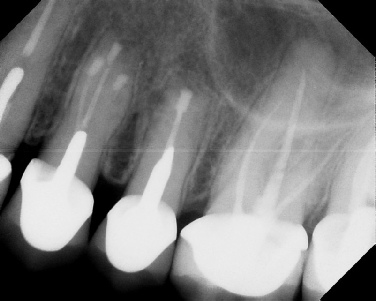

Apicoectomy - Surgical Root Canal Pre-op (post trauma) Coronal segments obturated Apical segments surgically removed 3 years